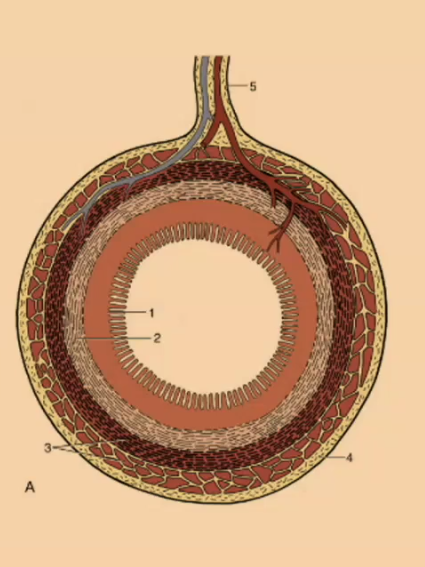

What is the outermost layer of the simple stomach?

Serosa

Serosa

What creates the mucosal folds in the simple stomach?

submucosa

What is the thinnest layer of the simple stomach wall?

Muscularis mucosa

What is the innermost layer of the simple stomach wall?

Mucosa

#1

Mucosa

#2

Submucosa

#3

Muscular (2 Layers)

#4

Serosa